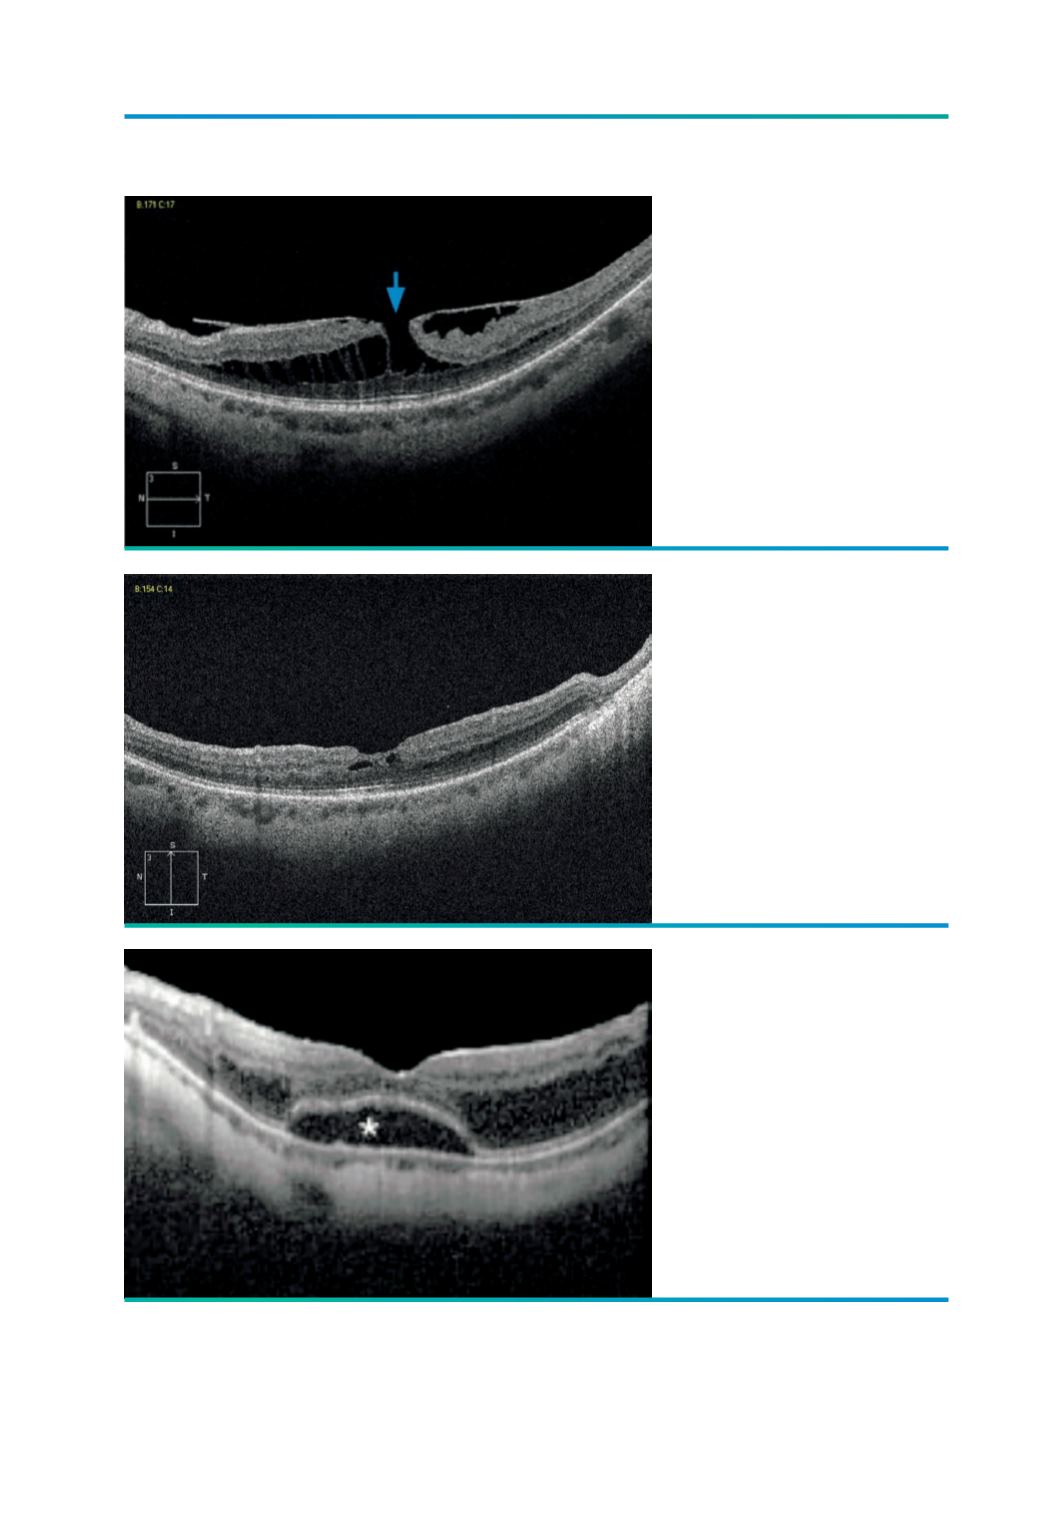

Figura 3.

3 meses após vitrectomia,

pelagem da MLI, tamponamento

com gás; acuidade visual

igual sem metamorfopsias;

encerramento do buraco com

diminuição acentuada da

espessura da retina.

Figura 2.

Miopia -10.75 D; Foveosquisis

com buraco lamelar (

→

), VOD-

4/10 cc, com metamorfopsia.

Figura 4.

Foveosquisis com descolamento

foveal (*).